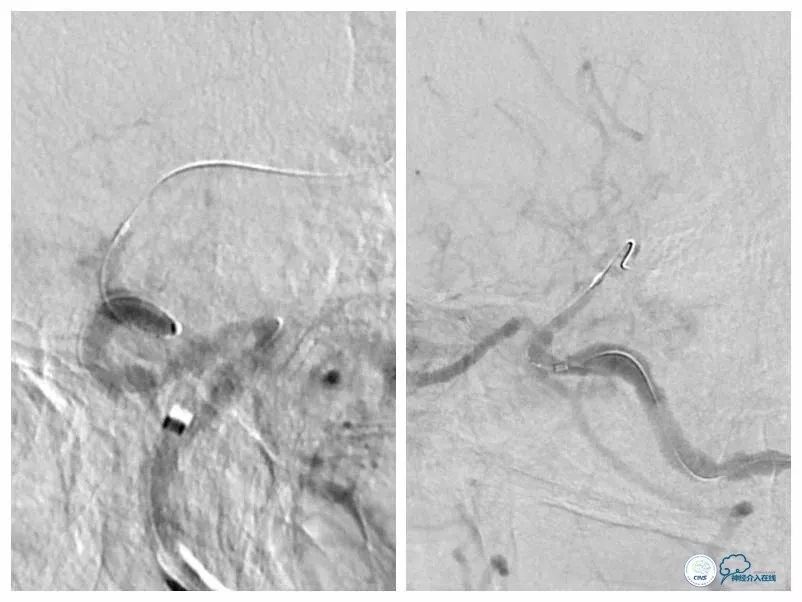

沿导丝送入两枚Apollo(2.5mm×8mm)球扩式支架由远及近释放(图11,12)。

图11

图12

本例患者狭窄程度较硬,微导丝通过病变后但微导管无法跟进,由于首过病变的微导丝系200cm短导丝,遂只能采用分节剪短微管方法撤出微导丝(图17)。

图17